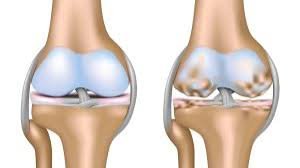

ما هو تآكل غضروف الركبة؟ ولماذا يُسبب خشونة الركبة؟

غضروف الركبة هو نسيج مرن يغطي أطراف العظام داخل المفصل، ويعمل كوسادة تمتص الصدمات وتسمح بالحركة السلسة.

عند حدوث تآكل غضروف الركبة تدريجيًا، تقل سماكته وتفقد الركبة قدرتها على الحركة الطبيعية، ما يؤدي إلى احتكاك العظام ببعضها، وهنا تظهر خشونة الركبة بكل أعراضها.

إذًا خشونة الركبة هي النتيجة المباشرة لتآكل غضروف الركبة، وليستا حالتين منفصلتين.

درجات خشونة الركبة

خشونة الركبة يمكن تقسيمها إلى عدة درجات بناءً على شدة الأعراض وتآكل الغضاريف، هذه الدرجات تساعد الأطباء في تحديد العلاج المناسب لكل حالة. إليكم تفصيل هذه الدرجات:

الدرجة الأولى

- ألم خفيف بعد المجهود

- تيبّس بسيط

- لا تظهر تغييرات واضحة في الأشعة

الدرجة الرابعة

- ألم شديد حتى أثناء الراحة

- فقدان كبير في الحركة

- تشوه في شكل المفصل

- تآكل شبه كامل أو كامل لغضروف الركبة